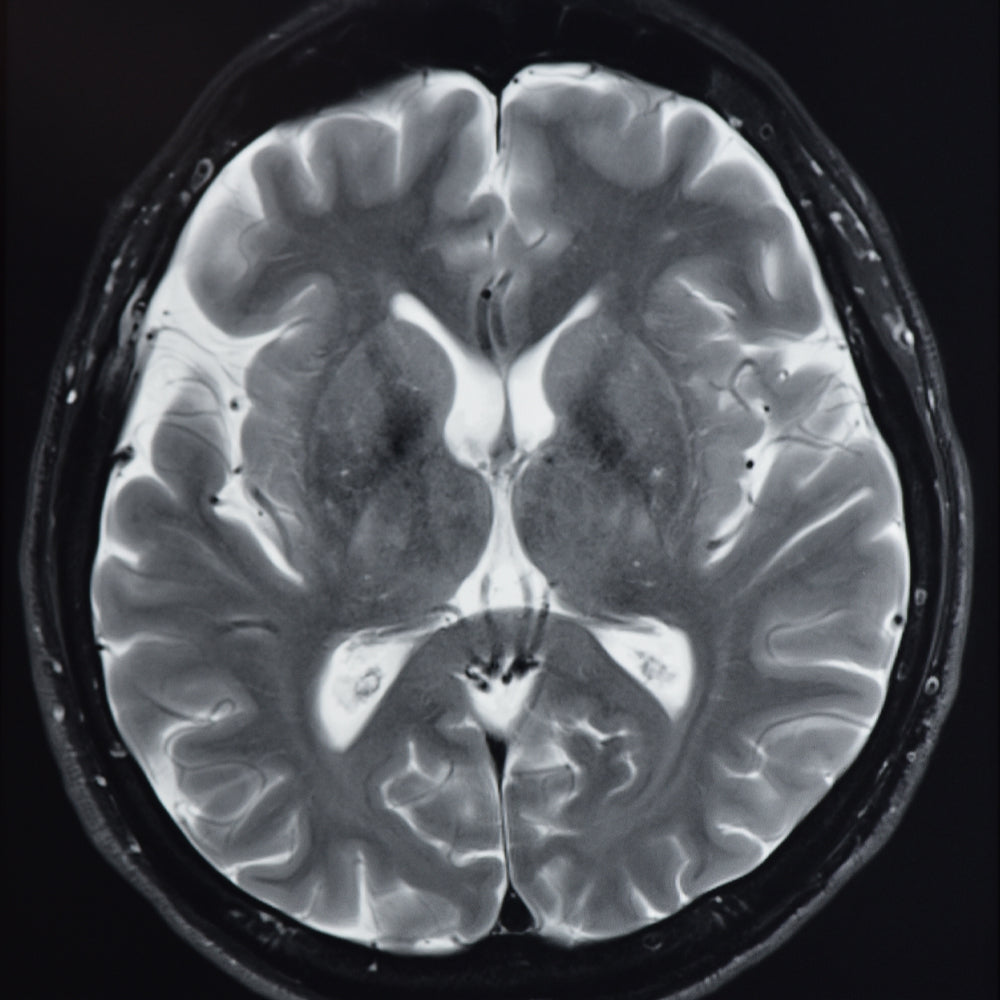

Our brain is a complex organ that uses neurotransmitters and neuromodulators to start, stop or change the body’s physical and psychological processes. This is two way communication, and receptors in the sensory organs and all over the body give signals to the brain for a multitude of functions. By choosing to respect the natural and physiological rhythms that control our sleep quality, we influence how our brain and body respond and, therefore, can create the optimal physiological conditions for good-quality sleep.